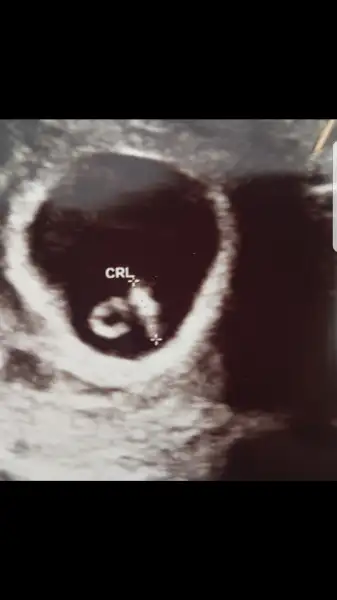

Maşallah bebek şeklini almış seninle aynı gün Doğum görünüyor ve adaşız :) geçen hafta 1 cm di usg baktırmıştım böyle görünmüyordu demekki bu hafta daha belirginleştiAh yavrum nasıl da tatlılar ya, şükürler olsun ben dün hem sana hem kendime dua etmiştim:) benim de bugün randevum vardi. hatta bebegi biraz daha net gördük. kanama alanı da düzelmis şükürler olsun ki. şaşkına döndüm gecen hafta 7.5mm idi bugün 1.5cm olmuş. 2 katina çıkmış. kalbi de 129 atiyordu 157 ye cikmiş :) hatta usg yi de paylasıyorum, masallah hepsine

geçen hafta benim kanamam oldu diye baktirmıştım okadar fark var ki. hatta 7.5 mm lik halinin de usg sini paylasayım, tahminen senin minigin de bu kadar büyümüştür :) bak geçen hafta ki hali ;Maşallah bebek şeklini almış seninle aynı gün Doğum görünüyor ve adaşız :) geçen hafta 1 cm di usg baktırmıştım böyle görünmüyordu demekki bu hafta daha belirginleşti

Ayy canım bu bebiş mi kuyruklu kuyruklu kıyamam ya Rabbim ne büyük nasılda yaratıyorgeçen hafta benim kanamam oldu diye baktirmıştım okadar fark var ki. hatta 7.5 mm lik halinin de usg sini paylasayım, tahminen senin minigin de bu kadar büyümüştür :) bak geçen hafta ki hali ;